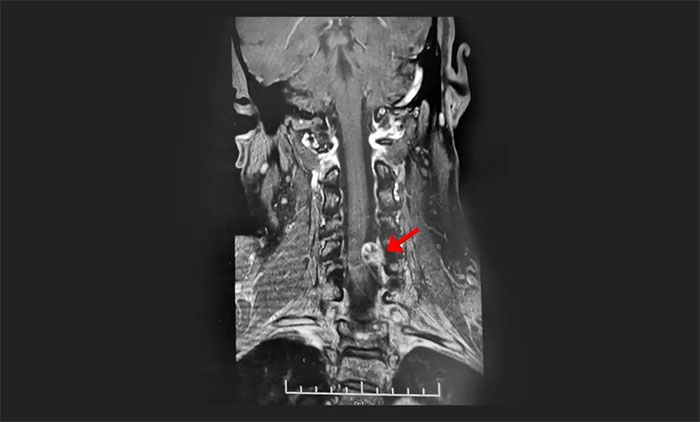

《湖北日报》2023年2月14日报道,60岁的陈阿姨两年前开始出现双上肢麻木的症状。陈阿姨以为是颈椎病,一出现症状她就自行服药,有时还去按摩,效果不明显。前段时间,陈阿姨左手臂麻木感越来越强烈,做家务都有点无力,还出现了胸部麻木和膝盖疼痛,这才在家人的陪同下来到当地市级医院求诊。经颈椎磁共振检查,显示颈髓椎管内肿瘤病变。

▲ 影像学检查是发现椎管内肿瘤较理想的方法

随着肿瘤压迫症状持续加重,患者还可出现明显的运动功能障碍。“一些患者以为患上了脑肿瘤或脑血管疾病,殊不知真正的元凶藏在椎管内。”于主任表示,通过脑脊液检查、CT及MRI影像学检查、脊髓血管造影等检查,是可以将椎管内肿瘤和颈椎病明确鉴别的。其中,CT或MRI检查能确定椎管内肿瘤的诊断,且能显示肿瘤与正常组织的界限、肿瘤大小与范围,是较理想的检查方法。但这仍然有赖于医生扎实的专业水平和丰富的临床经验。